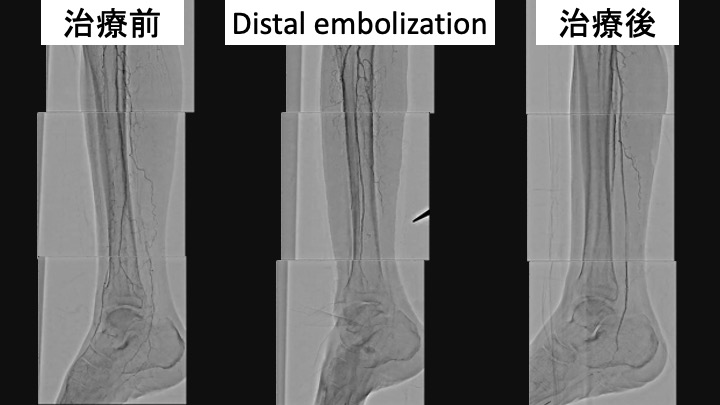

症例は70代男性、糖尿病性腎症で維持透析中である。右足趾の虚血性潰瘍を認めた。SFAにびまん性高度狭窄、ATA、PTAに高度石灰化を伴うCTOを認め、EVTの方針となった。午後6時に手技を開始した。ATAは石灰化に阻まれアンテからのワイヤー通過は不能、足背動脈を穿刺し、プルスルーを確立しバルーン拡張を行った。しかし、アンテのワイヤーが足背動脈遠位に通過せず、穿刺部での血管損傷のためATAから足背動脈への血流が途絶えてしまった。PTAは閉塞しているが、側副血行路経由で足底動脈の血流は確認できたため、SFAの治療を行い手技終了の予定とした。しかし、SFAをDCBで拡張したところ、遠位塞栓により足首以下の血流が消失した。繰り返し血管拡張薬を投与するも血流の改善認めなかった。そのため、PTAへのEVTを追加する方針とした。この時点で午後11時半であった。アンテからのワイヤーは通過せず、石灰化を目印にPTA遠位を穿刺し、ワイヤー通過に成功した。バルーン拡張後はPTAから足底動脈への血流が得られ、午前3時に手技を終了した。

結語:

DCBによる重度の末梢塞栓を経験した。CLTIでrunoffの乏しい症例でのDCBの使用は慎重に検討しなければならない。